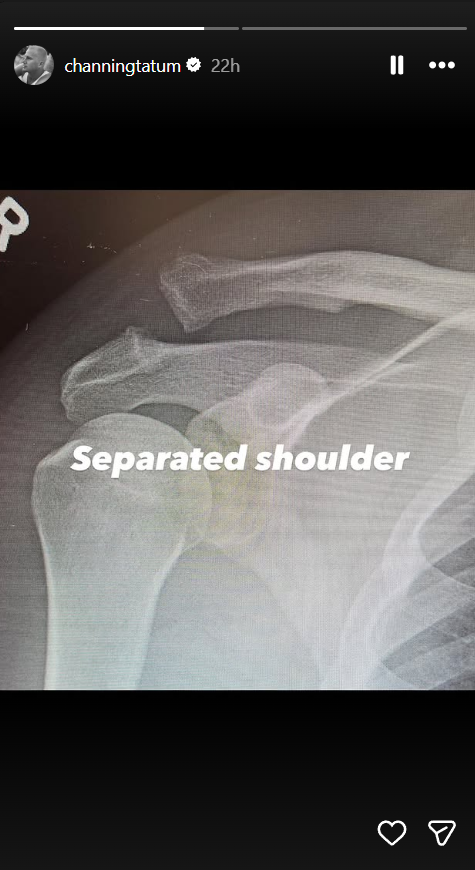

Tatum followed the initial post with X-rays on Instagram Stories, showing a clear shoulder separation.